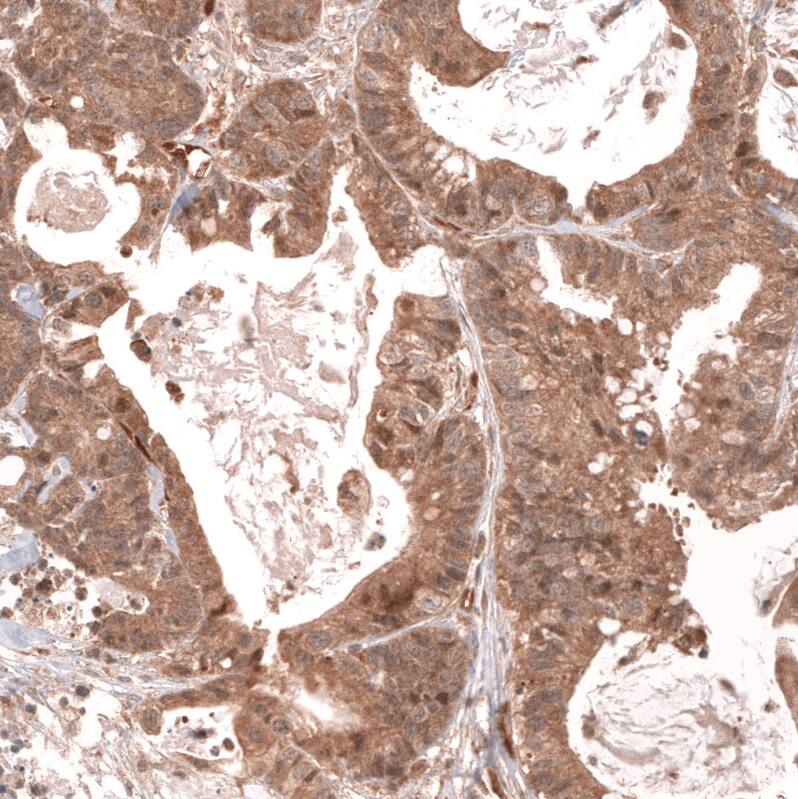

Staining of human colorectal cancer shows moderate cytoplasmic positivity in tumor cells.